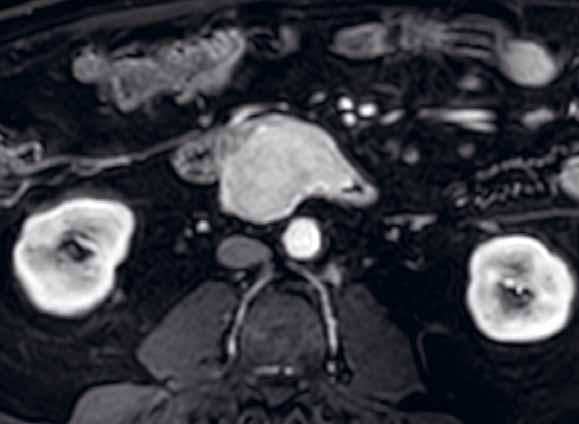

2.3 CT

V dnešní době je CT vyšetření plně dostupnou metodou v komplexním hodnocení orgánů břišní dutiny, čehož se využívá i pro vyšetření střev.

CT umožňuje zobrazit postižení střevní stěny i změn v okolí trávicí trubice (absces, zánětlivý infiltrát, postižení mezenteria, píštěle, fibróza, lipomatóza atd.). Výhodou současných multidetektorových přístrojů je možnost rychlého náběru dat ze submilimetrových řezů, s možností automatické derivace dat ve více rovinách, a tím i možností multiplanárního zobrazení.

Tenké střevo můžeme hodnotit v CT obraze v rámci cílených vyšetřovacích protokolů i v rámci necíleného vyšetření břišní dutiny. Necílená vyšetření ovšem nemají stejnou senzitivitu a specificitu jako vyšetření cílená. Při necíleném vyšetření nemusí být distenze střevních kliček optimální. Posouzení střevní stěny může ovlivnit také volba perorálně aplikované kontrastní látky, kdy například použití pozitivní kontrastní látky per os snižuje možnost posouzení samotné střevní stěny. U nativně prováděných CT vyšetření (například u ileózních stavů, alergií na kontrastní látku aj.) je hodnocení střevních patologií také značně limitované. Na nativních CT skenech lze posoudit jen výrazněji zesílenou stěnu střevní, dilataci střevních kliček, edém řas, volnou tekutinu v dutině břišní. Pro cílená vyšetření tenkého střeva využíváme speciální vyšetřovací protokoly.

Volba vyšetřovacího protokolu, typ a způsob aplikace kontrastní látky závisí na tom, co chceme daným vyšetřením zjistit. Jiný je způsob vyšetření CT břicha k vyloučení tekutinových kolekcí nebo například pro potvrzení dehiscence anastomóz. Odlišný protokol má taktéž CT enterografie, kdy je podezření na píštěle či abscesy, či je vyšetření prováděno v akutním stavu pro ileus při klinicky významné stenóze. Vyšetřovací protokoly jsou standardizovány. Pracoviště se řídí místními radiologickými standardy, které jsou v souladu s národními radiologickými standardy. Místní radiologické standardy obsahují jednotlivé vyšetřovací protokoly (rozsah vyšetření, způsoby a množství aplikovaných kontrastních látek, jednotlivé fáze vyšetření atd.). Vyšetření dutiny břišní se ve většině případů provádějí s aplikací kontrastní látky – a to orálně, intravenózně, rektálně či instilací do dutinových formací. Kontrastní látky aplikované do trávicí trubice můžeme rozdělit na hyperdenzní (jodové kontrastní látky, baryová suspenze) (obr. 1) a hypodenzní (voda, manitol, vzduch) (obr. 2). Intravenózně se u výpočetní tomografie podává výhradně jodová kontrastní látka. Pro přesné načasování vyšetření v arteriální fázi (CT angiografie) se užívá metoda bolus trackingu, kdy během aplikace kontrastní látky přístroj skenuje nízkodávkovým skenem zvolený objem a vyšetření spustí až po dosažení prahové hodnoty denzit. Perorálně se aplikuje ředěná jodová kontrastní látka, voda či roztok manitolu.